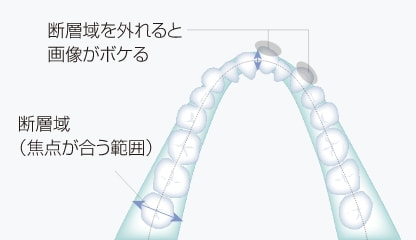

パノラマ画像がボケる理由

患者さんごとに形態が異なる歯列弓を、焦点が合う限られた断層域に正確に合わせるためのノウハウが求められます。

3Dオートフォーカス技術でのフォーカス域

フォーカス域27mmの断層情報により歯列弓形態の個人差や位置付け時のズレにも柔軟に対応し、歯列全体にピントの合った画像が得られます。